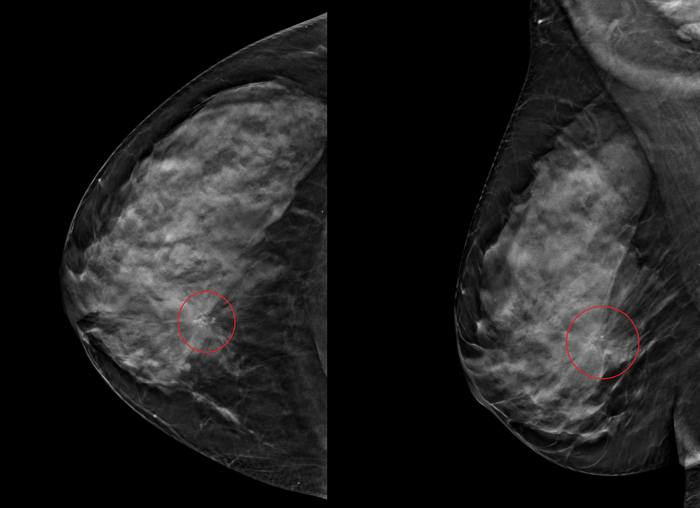

Итак, пациентка 56 лет, обнаружила и себя узел в правой молочной железе, с чем обратилась к гинекологу для дальнейшего обследования. Была направлена на маммографию, где, на первый взгляд, ничего трагического видно не было

Однако обращала на себя внимание группа микрокальцинатов на позиции примерно 2-3 часа (медиально или с внутренней стороны):

Которые стали более отчётливыми на томосинтезе (специальная техника получения "объёмного" изображения) с нарушением арxитектуры молочной железы в данном участке: